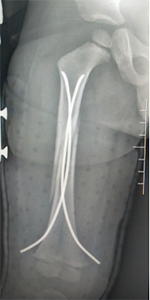

儿童股骨干骨折的微创弹性髓针固定技术:

儿童股骨干骨折的微创弹性髓针固定技术(术后伤口外观仅缝合两针)